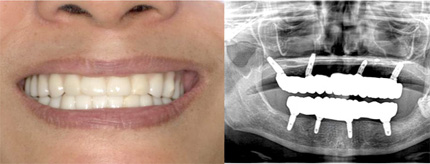

オールオン4の治療例:1

治療前

治療後

オールオン4の治療例:2